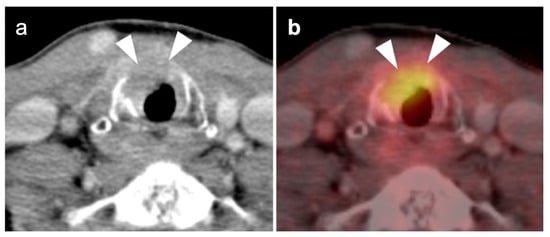

2.6. Thyroid Cancer

- Anaplastic thyroid cancer